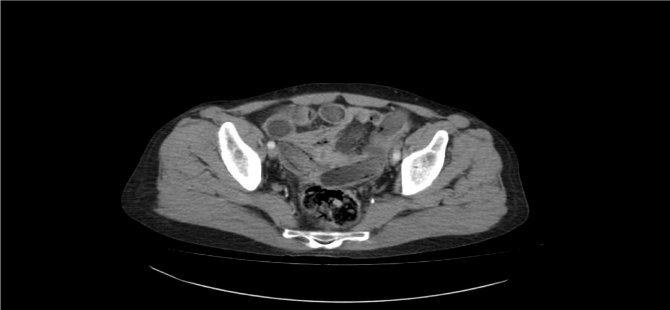

Polis, şahsın midesinde eroin olabileceğinden şüphelenip hemen hastanenin gastroenteroloji bölümüne götürdü. Burada tomografisi çekilen midede, sosis büyüklüğünde paketler tespit edildi. Ancak polis, emin olmak için daha sonra şahsa endoskopi işlemi de yaptırdı. Bu sayede ucunda ışıklı küçük bir kamera bulunan ve endoskopi adı verilen bir cihaz yardımıyla şahsın yemek borusu, mide, onikiparmak bağırsağı ve kalın bağırsaklarında 49 paket sosis büyüklüğünde paketler olduğu kesinleşti.